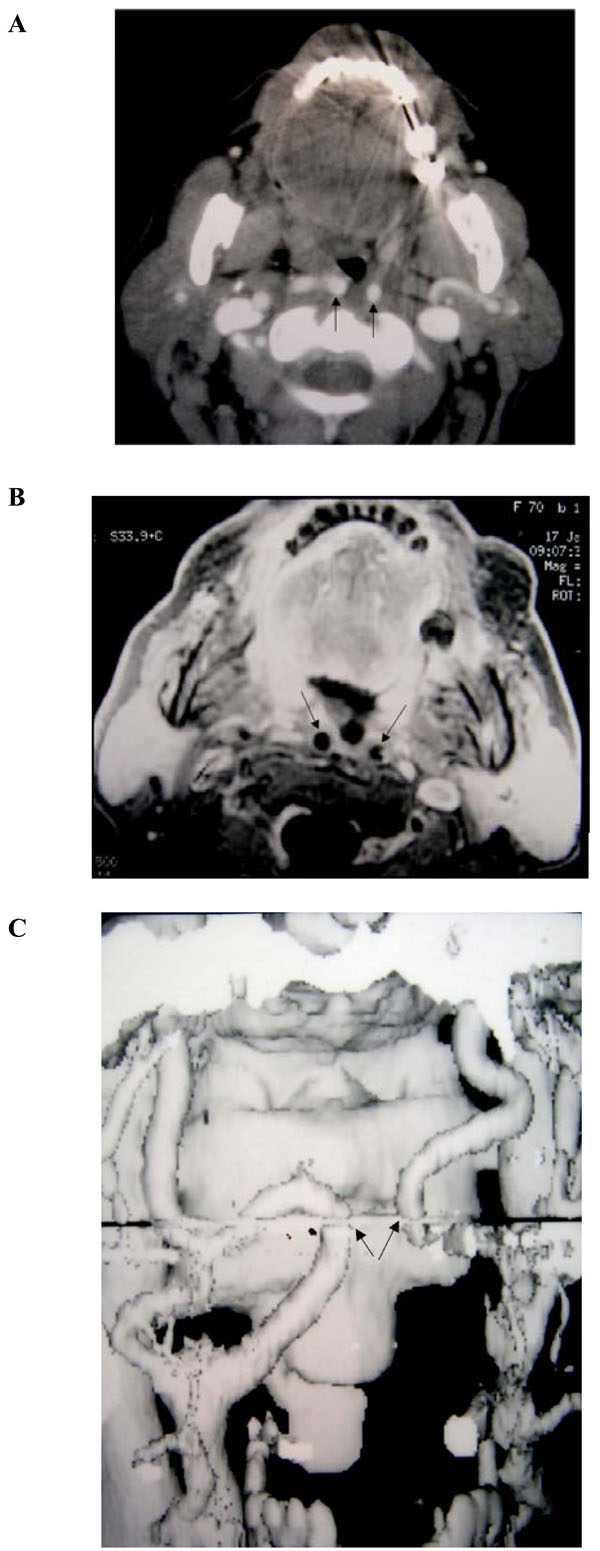

(4A-C). Focal bilateral course of both internal carotid arteries at the level of the oropharynx (patient # 11).

A and B: Axial enhanced CT and enhanced T1-weighted (600/12; TR/TE) MR scans through the oropharynx shows bilateral medialization of the course of both ICA´s (kissing carotids), running in the retropharyngeal space.

C: Maximum Intensity Projection (MIP) from axial sources images of CT and MR show medialization of both ICA´s, with abrupt change in the course of both arteries at the level of the oropharynx and, thereafter, upper regaining its normal course (arrows).

(Radiological classification of this patient was considered A,2).